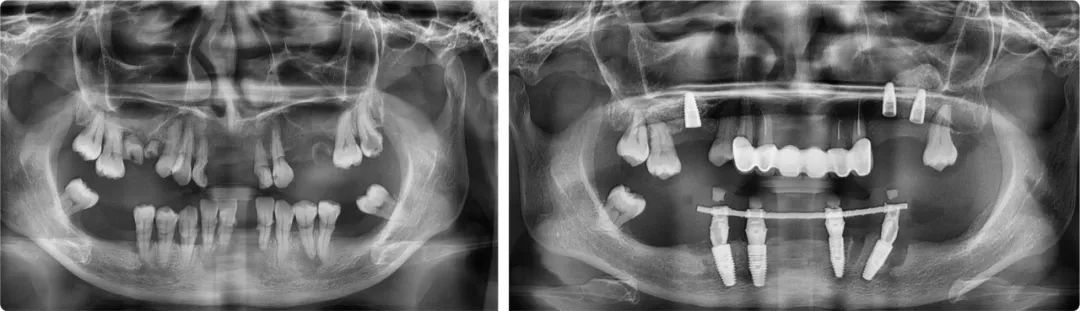

“由于患者后牙牙槽骨垂直性吸收,拔牙后需要種植的位置距離神經管太近,無法種植。為解決這個問題,前牙區的四顆我采用了傾斜種植,盡量把修復的牙位往后移,彌補她后牙區的咀嚼功能。”

手術中,謝海洋通過數字化導板精準定位,避開頦孔和下牙頜神經管,完成了下半口即拔即種治療。“有兩個種植點位一側是神經管,一側是之前種植的植體,位置不容有一絲偏差,否則要么種植失敗,要么造成不可逆轉的下唇麻木。”術后CBCT顯示,種植體距離神經和頦孔0.3-0.5毫米,屬于安全距離內。

患者術前術后全景片